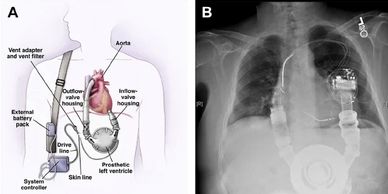

Our client had developed an active implantable device targeting a critical cardiac condition — a high-stakes program where safety architecture directly determines patient outcomes. 4ms was brought in at the risk management phase, leading a rigorous DFMEA process that mapped failure modes across the full system.

What distinguished this engagement was what happened next: the DFMEA didn't just document risk — it drove design. Identified failure modes led to concrete mitigations, with 4ms designing and implementing a portion of those mitigations directly, others developed by the client, and others built jointly. This deeply embedded co-development model ensured safety was engineered into the architecture, not added as a layer on top. The device is now in clinical studies.

4ms contribution:Risk assessment leadership, DFMEA facilitation, design mitigation development — embedded at the intersection of safety engineering and product design.